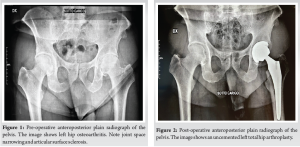

A 62-year-old male patient underwent a primary uncemented THA by direct anterior approach in June of 2020 due to the left hip end-stage osteoarthritis (Fig. 1). After 4 days, the patient was discharged home without complications (Fig. 2).

In January 2021, the patient presented with groin and buttock pain at rest and during walking, with limited range of motion (R.O.M) but with no symptoms of inflammation. MRI examination showed the presence of a voluminous three-lobed fluid-filled cyst around the implant (Fig. 3). Synovial fluid was aspirated (23 ml) and four samples were collected for cultures, all of them yielding negative results. In February 2021, the patient underwent arthroscopic synovectomy. After 1 month of follow-up, he underwent a new MRI, which showed the presence of a new voluminous cyst around the implant surrounding the nervous-vascular bundle causing paresthesia on the medial side of the thigh, and showed the same characteristics as the previous one. Subsequently, he was admitted to the hospital and a complete open resection was performed with femoral and obturator nerves neurolysis. Several samples were collected for cultures, all of them yielding negative results. The patient presented good hip function, but complained of persistent groin pain. After 7 months, he underwent 111 Indium-labeled white blood cell bone scan which documented a high leukocyte uptake around the greater trochanter. In October 2021, he underwent a new ultrasound which showed the presence of a new voluminous cyst (50 mm × 15 mm) around the implant with the same characteristics as the previous one. Synovial fluid was aspirated (20 ml) and sent for cultures. Cultures were negative. In November 2021, he was admitted for further examinations. PET-CT showed presence of increased uptake around the ileo-psoas and vastus lateralis muscles. A new ultrasound showed the presence of a voluminous cyst (42 mm × 10 mm) around the implant, and blood test revealed ESR of 42 mm, and C-reactive protein (CRP) level of 0.58 mg/dl. In January 2023, he underwent triple phase bone scan that showed increased activity isolated to the proximal femur around the femoral stem. Since there were no clear signs of infection, an isolated single stage femoral stem revision was performed in February 2023. During the surgery, several swabs were collected and sent for culture. All three samples came positive for S. caprae. As per infectious disease consultant’s recommendations, the patient was treated with 100 mg oral minocycline twice a day for 4 weeks. Two months after surgery, the patient complained of groin and buttock pain. Inflammatory markers were elevated (CRP 47.30 mg/dL), and a pelvis MRI showed a fluid containing formation with the same characteristics as the previous MRI (Fig. 4). In June 2023, he underwent a new ultrasound which showed the presence of a new voluminous cyst around the implant with the same characteristics as the previous one. Synovial fluid was aspirated (18 ml) and sent for cultures. Cultures revealed the presence of S. caprae; susceptibility to rifampin and minocycline was confirmed, which prompted the infectious disease consultant to initiate these antibiotics. The patient started taking 100 mg oral minocycline twice a day and 600 mg oral rifampin once a day. At this time, the decision was made to opt for the two-stage revision prosthesis.